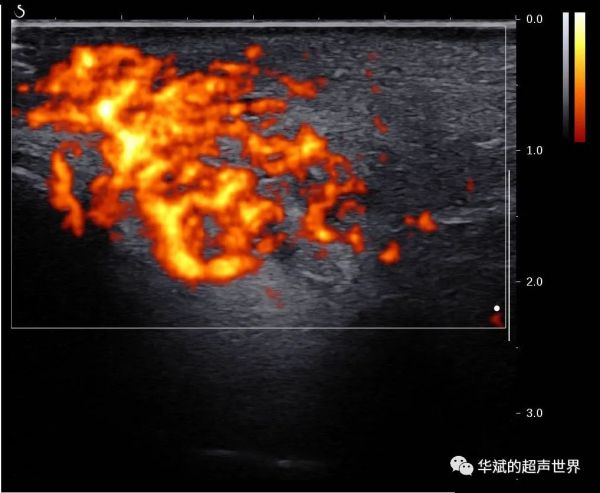

我们对该区域行超声检查,发现局部皮下组织和腮腺的后上部分内为大量的蜂窝状回声,彩色多普勒和能量多普勒均显示其内为及其丰富的血流信号(酷似血管瘤),可探及低速动脉血流。(下三图,PA:腮腺)

我们推测,腮腺内及腮腺周围的这些病变也可能是艾瑞卡引起的血管增生症的表现,尽管之前的研究中仅仅提到这种反应性毛细血管增生症主要发生在皮肤和粘膜。这一病例提示我们在艾瑞卡使用者中,其他深层组织内也可能会出现反应性毛细血管增生症。